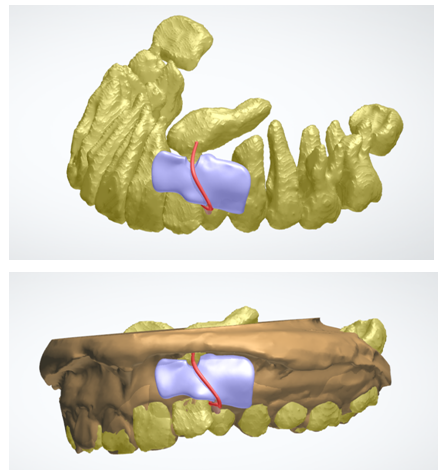

3、埋伏牙数字化导航开窗牵引

利用口腔扫描模型+CBCT三维定位,精确定位埋伏牙开窗位置,并设计牵引装置高效解决埋伏牙问题。